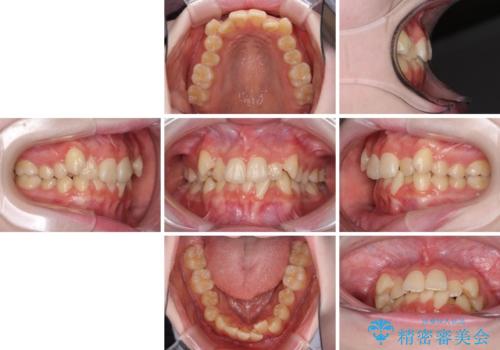

- 上下前歯のデコボコを気にして来院された患者様です。

前歯の叢生は強かったのですが、口元が引っ込んでいる印象であったため、非抜歯にて矯正治療を行うこととしました。

インビザラインでの自己管理は難しいとのことで、ワイヤー装置にて矯正を行うこととしました。